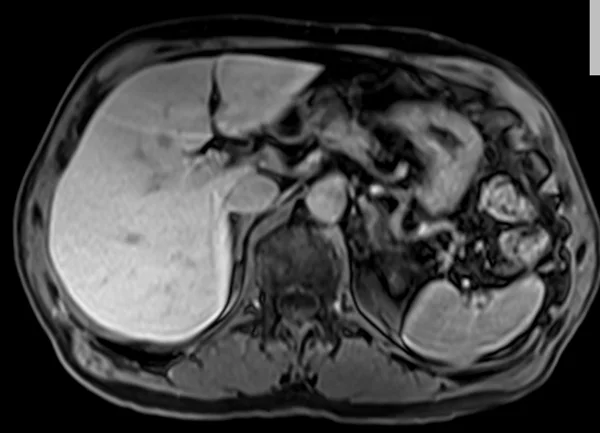

delay 5min 1 - MRI

delay 5min 2 - MRI

delay 5min 3 - MRI

delay 5min 4 - MRI

delay 5min 5 - MRI